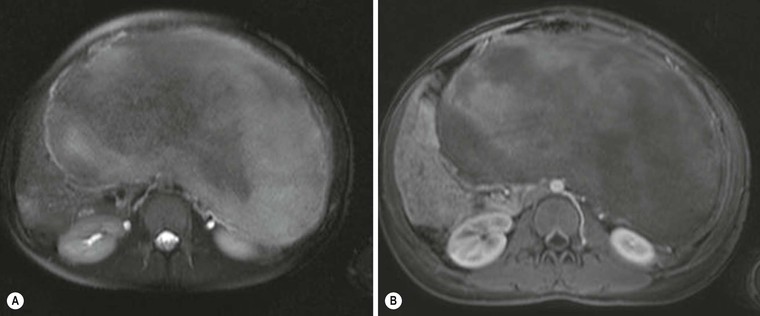

Hydatid disease is most commonly due to Echinococcus granulosus. Peritoneal hydatidosis is usually the result of traumatic or surgical rupture of hepatic hydatid disease and results in cystic, usually septated, thin-walled space-occupying lesions.12 CT is the method of choice in peritoneal seeding (Fig. 30-6). A calcifying rim is a suggestive feature. Ultrasound is useful for the detection of membranes, septa and hydatid sand within the cyst.